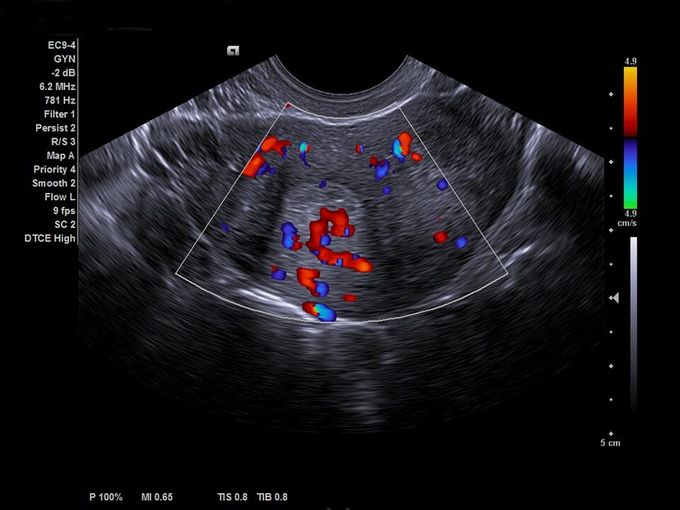

Кроме новой техники, можно заказать восстановленные медицинские системы: ультразвуковые сканеры, томографы, флюороскопы, ангиографы и хирургические установки С-дуга.